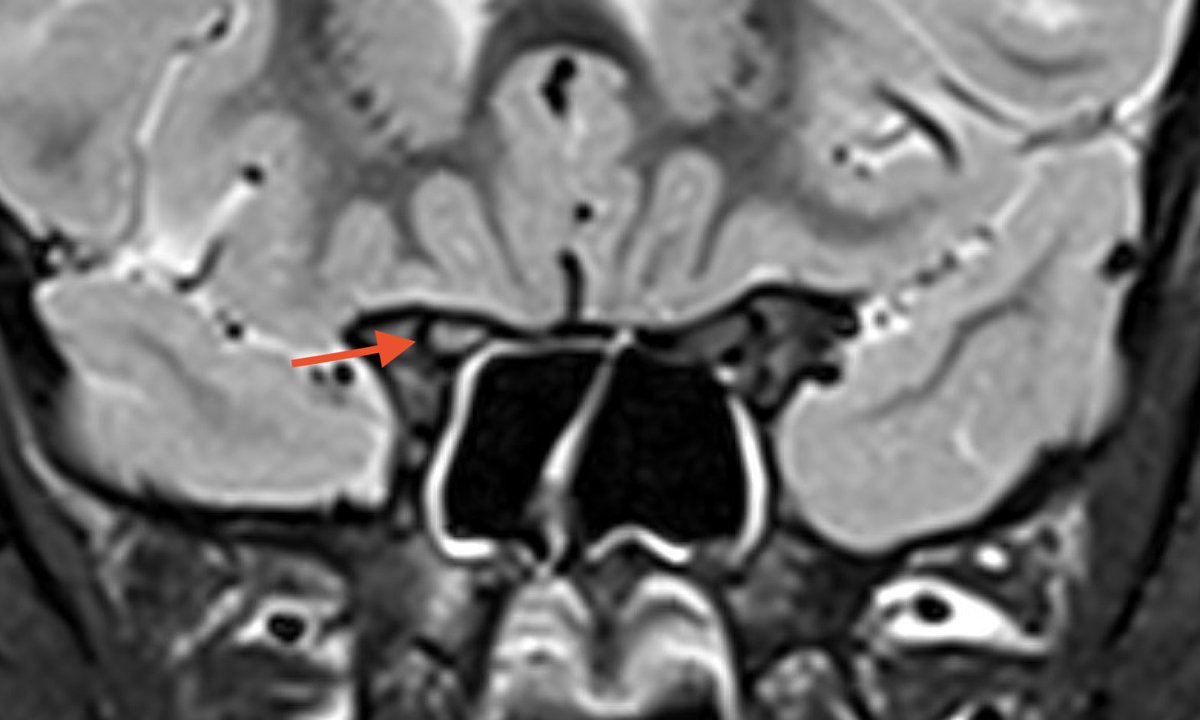

I’m not nice so I won’t tell you the eye exam but here is the MRI. Describe what you see… #childneurology

If you are having a rough time deciding whether or not the optic nerves are enhancing, you're not alone. @Dr.GlenTung always reminds us to use the coronal T2 with fat suppression to evaluate for optic nerve edema...@daniel_gewolb agree?